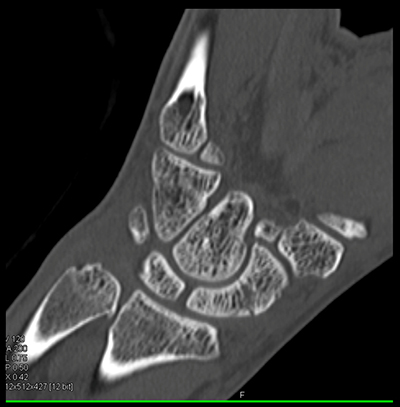

The best diagnosis in this case is

acute scaphoid fracture

trapezoid fracture

radius fracture

chronic scaphoid fracture